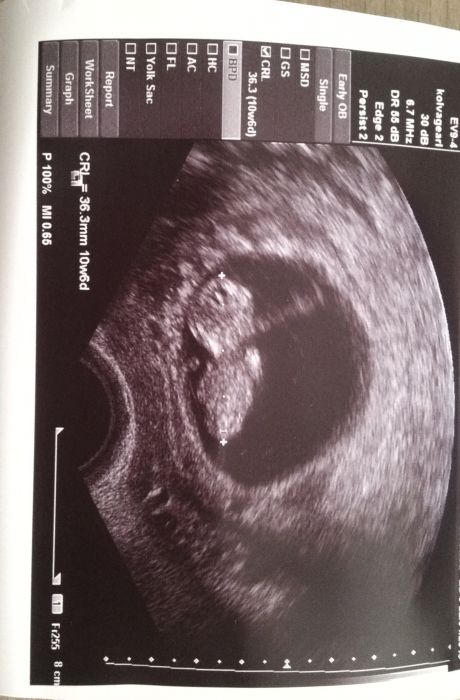

Autor: Verča 18.6.2015 v 15:38

Ahojky holky,tak mám po kontrole a jsem spokojená jak želva ;) Vyfasovala jsem průkazku takže jsem ofiko těhotná a zase jsem se mohla pokochat tím naším broučkem.pan doktor mi udělal radost,pry vypadáme na kluka ;) přikládám sem i naše foto,akorat je trošku maznuty...prďolka se tam furt vrtěl a nešel pořádně zaměřit :-D. Jinak si maličký nahnal další 2 dny do plusu takže už jsme starší o 14 dni přesně a tím se prý i budeme řídit. Termín porodu se mi tím pádem posunul z 22.1. na 8.1. Příští týden jdu na screening, prý stojí 1000 Kč ale moje pojišťovna to naštěstí hradí celé. ;) Tak snad bude všechno v pořádku.